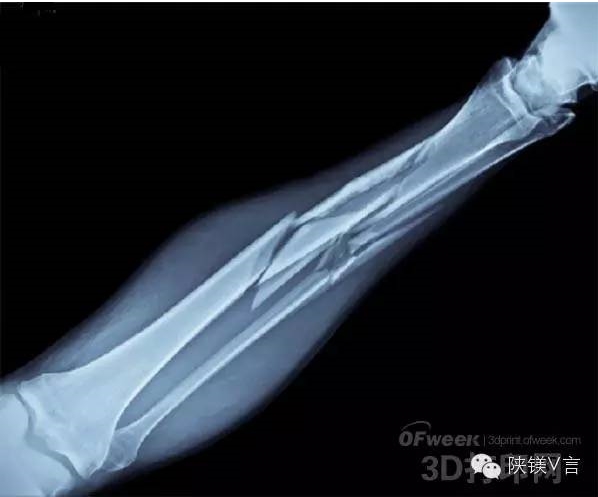

世界断骨愈合技术取得重大突破 镁合金3D打印支架研究令人兴奋

如今,断胳膊断腿似乎都不是很严重的问题,因为大部分都很容易医治,对伤者不会造成任何持久的影响。但是,有时候一些严重的伤势,往往需要在患者体内打上钢钉之类的帮助受伤骨愈合。这些植入物长时间留在人体内,有时候会产生比较严重的副作用,比如感染、关节炎等。为此,美国匹兹堡大学的研究人员一直在努力寻找一种方法来使用3D打印技术,以便更好地修复断裂,断裂的骨头,而无需使用金属钉之类的。近日,他们似乎已经找到了解决方案。

另外,研究人员也正在研究将合金用于3D打印支架。可以被人体吸收,并拥有与谷歌相似的性质,因此是一种辅助断骨愈合的理想材料。令人兴奋的是,研究人员已经找到一种方法来决定合金在骨折处溶解的速率。

由于还没有得到FDA的批准,因此相对比较难以商业化。但是Kumpta相信它的使用可能是非常有益的,尤其是对于那些更为严重的骨折或骨断裂患者。合金支架搭配这种“腻子”材料可能意味着严重的骨折可以更有效地处理,而无需后续手术以除去目前用于治疗严重骨折的金属板。